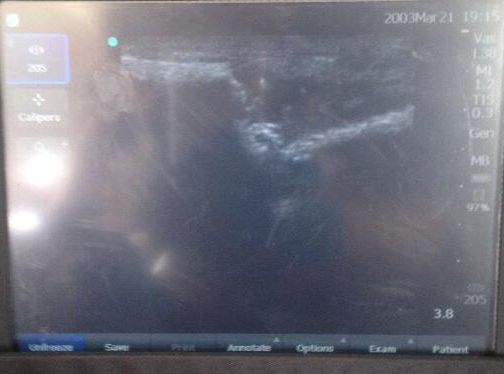

We have medical imaging in our Flying ER